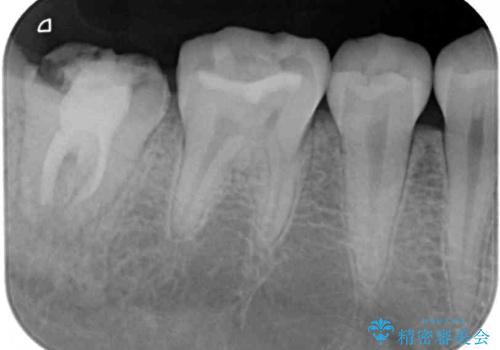

- 奥歯のかぶせものが頻繁に脱離することを気にされて来院された患者様です。

歯の高さが低く、かぶせものを安定して維持させることができないため、歯冠長延長術により歯の高さを増大させた上で、オールセラミッククラウンにて補綴することとしました。

クラウンが外れている期間も長く、虫歯が進行していたため、根管治療も行うこととしました。